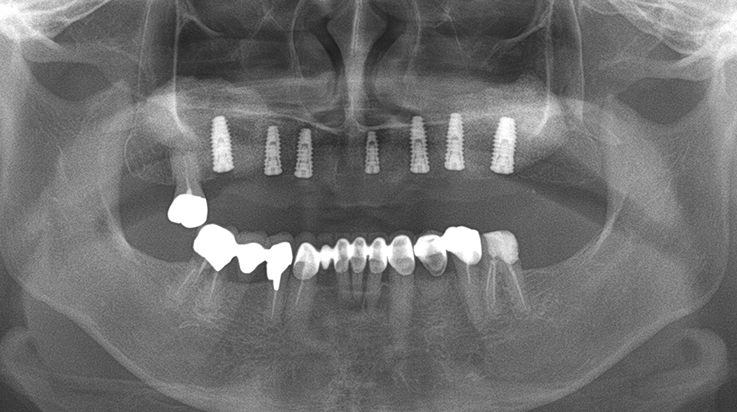

Implants/Bone Grafting

Fully edentulous clinical cases